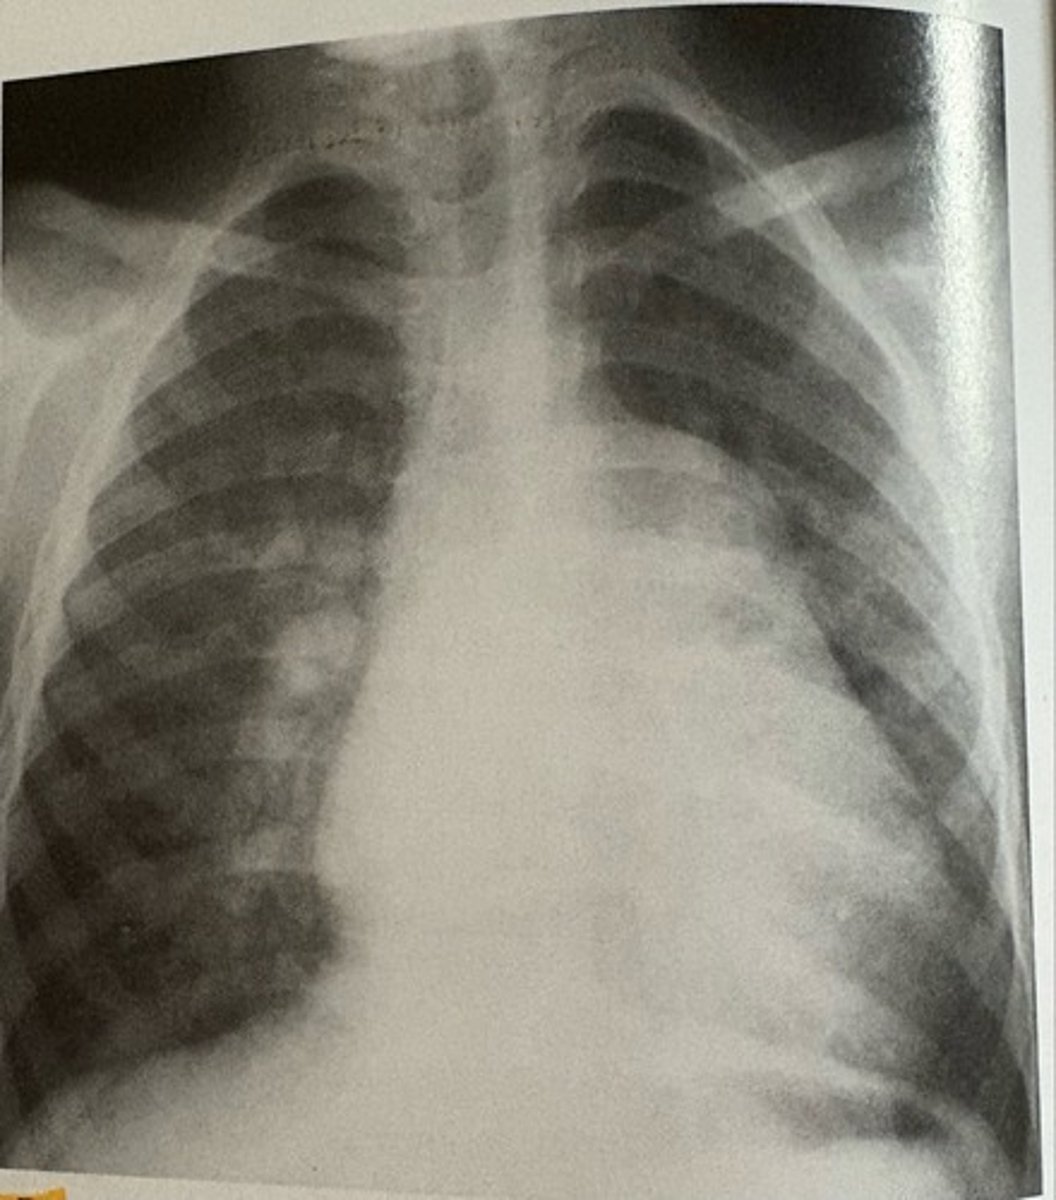

pericardial effusion

what pathology is present?